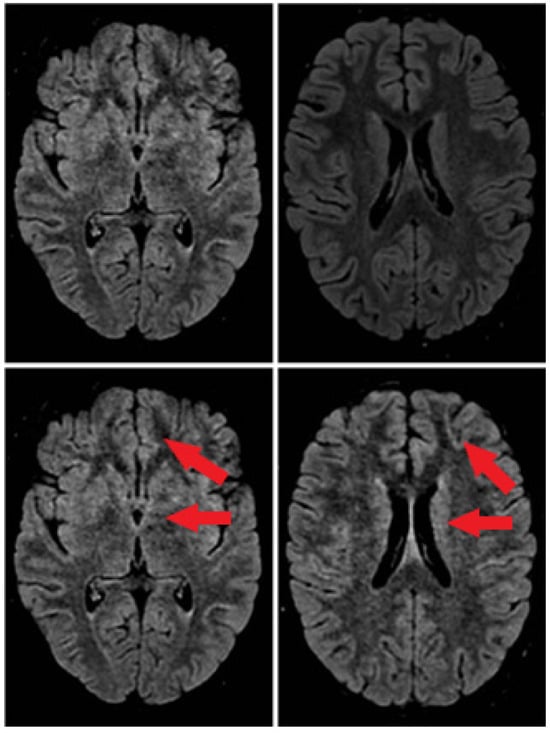

On day 11, a cerebral MRI was repeated showing predominantly left frontal cerebritis foci (see Figure 1).

Figure 1.

Brain MRI. At the onset of the disease (first line). After 11 days of disease (second line).

There is no gold standard for the diagnosis of BBE. Lumbar puncture is a high priority test for suspected central nervous system disease [16]. CSF analysis shows albuminocytological dissociation or pleocytosis [15,17]. Abnormal EEG findings indicated central nervous system involvement, demonstrating impaired consciousness. EEG changes correlate with the level of consciousness in patients with BBE and often show predominant N1 and/or N2 sleep patterns [18]. As shown previously, these characteristic EEG changes are possibly caused by dysfunction of the ascending reticular activating system (ARAS) [18]. ARAS is part of the brainstem reticular formation, and dysfunction of which is considered to be the cause of impaired consciousness in BBE. SEPs results suggest the interruption of the somatosensory pathway within the brainstem. MRI is the gold standard technique for brain imaging in encephalitis [19]. In BBE patients abnormal MRI lesions, such as high-intensity areas on T2-weighted images of the brainstem, thalamus, cerebellum and cerebrum, are characteristics [20]. All of these diagnostic data were found in our case report.

In our case, the diagnosis of BBE was based on typical symptoms, such as external ophthalmoplegia, ataxia, and disturbance of consciousness. Typical MRI images (high signal lesion on T2-weighted images located in the brainstem) and high titers of anti-ganglioside antibodies may contribute to the diagnosis of BBE.